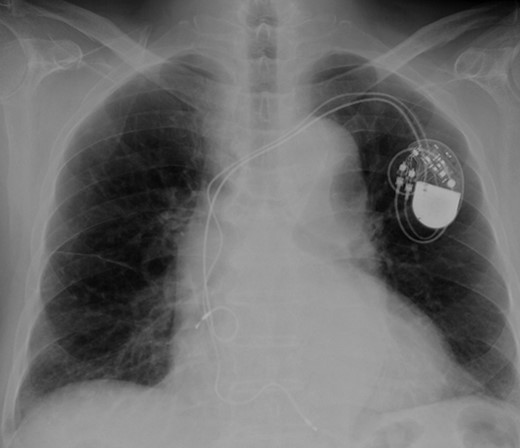

According to the current guideline for pacemaker infection, it was decided to remove the whole pacemaker system, including the two leads. Since implantation of new transvenous leads seemed undesirable because of ongoing active endocarditis, it was decided to implant epicardial leads on the left atrium and left ventricle via a left mini thoracotomy. Because the patient had complete AV block without any spontaneous R wave, a new DDD pacemaker system was implanted first. The atrial lead was implanted on the appendage of the left atrium, and the ventricular lead was implanted onto the lateral wall of the left ventricle near the first obtuse marginal branch (Fig. 3). The old infected pacemaker system was then explanted by percutaneous extraction.